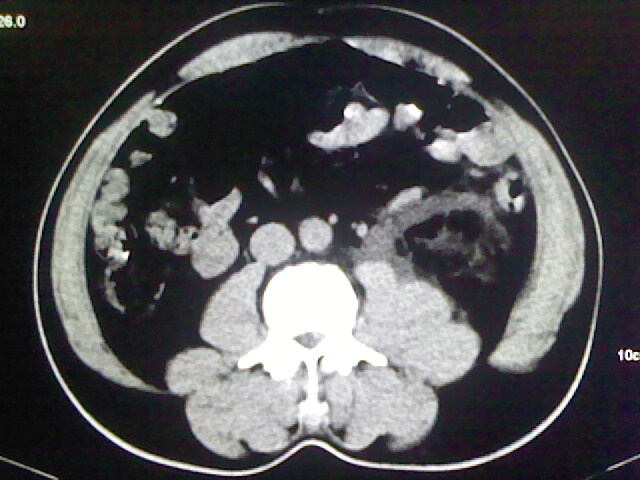

以下是引用zsl6918在2009-2-7 7:29:00的发言:[br]请提供介入的方式方法,肾及输尿管改变考虑与介入损伤有关,漏了,尿液外渗。

以下是引用余辉在2009-2-7 8:27:00的发言:[br]可能是硬化剂烧穿囊壁进入肾盂输尿管了,尿漏。不除外介入或碎石术后合并感染[br]患者术后怀疑结石,接着就碎石了?就怀疑没有确诊吗?碎石用的什么方法?气压弹道还是体外超声?如果这样的话责任人都难找

以下是引用随光逐影在2009-2-7 8:46:00的发言:[br]支持3楼意见。[br]另:不排除左肾及肾周感染可能。